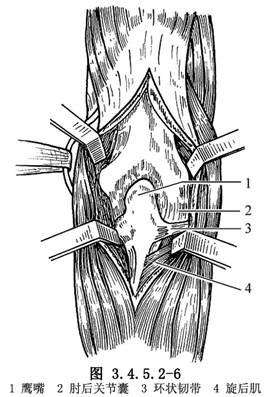

(2)切開深筋膜後,沿肘後肌與尺側腕伸肌之間切開並向兩側牽開,顯露後關節囊(圖3.4.5.2-5,3.4.5.2-6)。